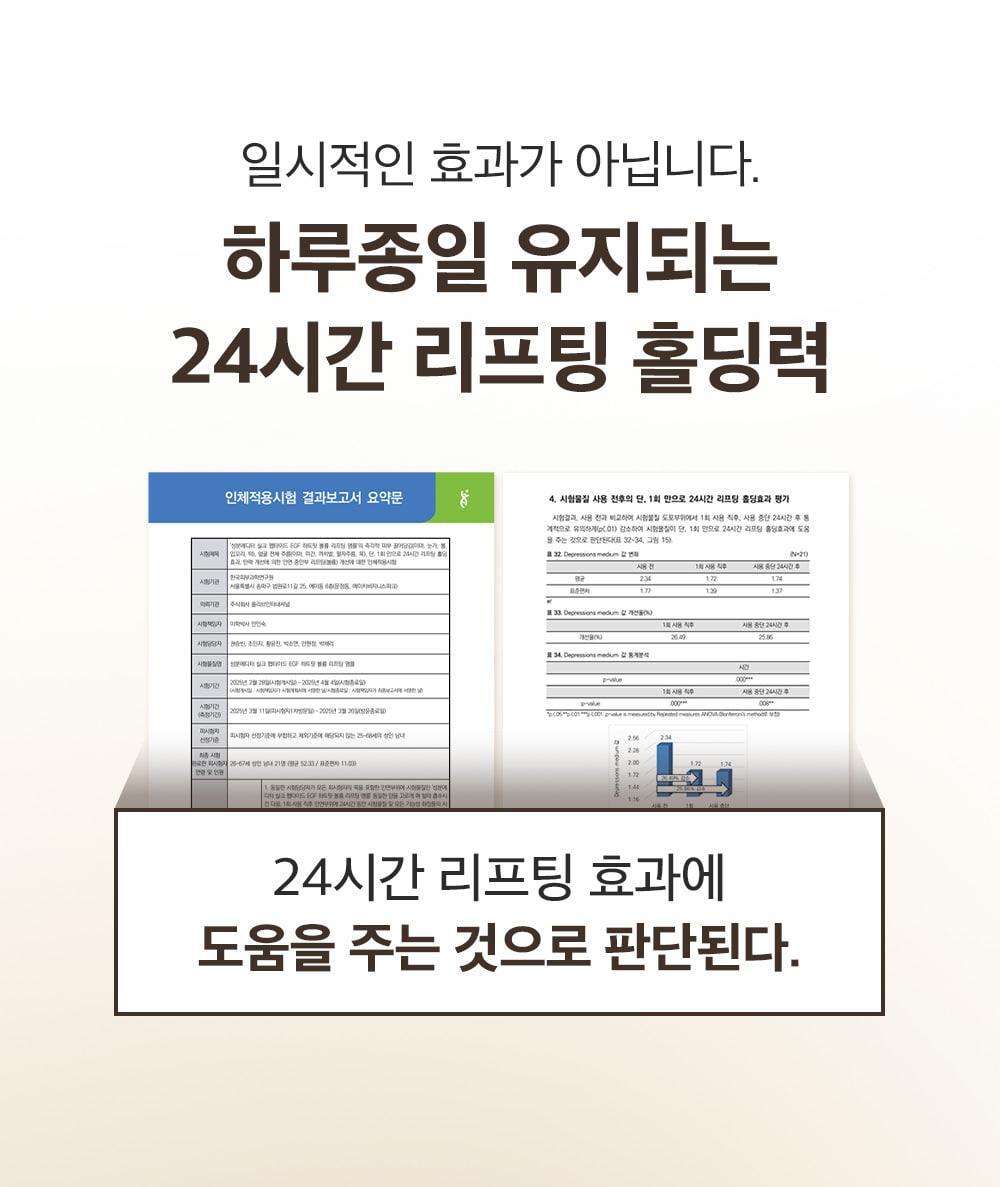

- 已完成人體應用測試。單次使用即可感到提拉緊緻效果。而且這不是暫時的效果。 24小時持續提升力量。持續用更見效果。